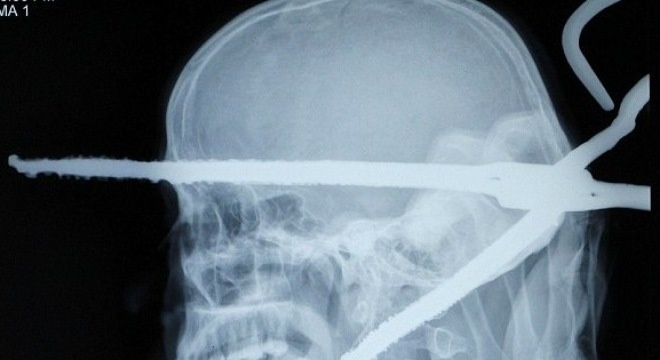

| Thắt lưng và vải mắc kẹt trong ngực Anuj Ranjan, 16 tuổi ở Ấn Độ, sau một vụ tai nạn. Ảnh minh họa: Toptenz |

Năm 2006, Anuj Ranjan, 16 tuổi ở Ấn Độ, gặp tai nạn gây ra một vết thương lớn ở bụng. Năm 2010, cậu vào viện vì bệnh lao và nhiễm trùng ngực. Trong quá trình phẫu thuật cho Ranjan, các bác sĩ tìm thấy một đoạn thắt lưng dài 20 cm và một số mảnh vải nằm giữa tim và phổi bệnh nhân, nguyên nhân gây nhiễm trùng, The Times Of India đưa tin.